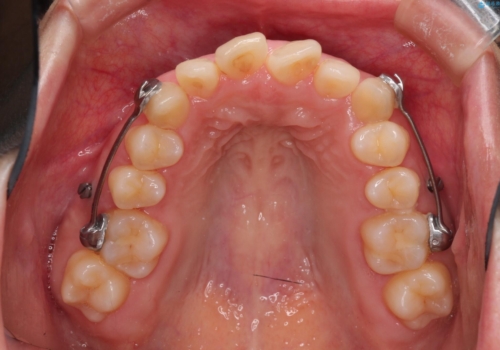

初診時の歯並びの状態としては、上下とも前歯部の中等度のがたつきがあり、その他に奥歯の噛み合わせのズレや、口元の突出感も認められました。

奥歯の嚙み合わせのズレを改善するにあたり、カリエールディスタライザーという装置を併用することで治療期間の短縮を図りました。